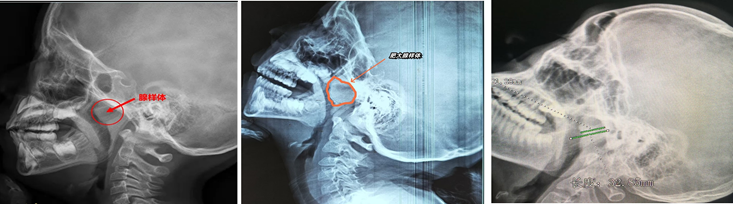

首先 观察症状:长期打呼噜、张口呼吸、听力下降等。其次到医院检查:医生可以用鼻内镜查看腺样体大小;或者X光或CT:评估腺样体堵塞程度(通常堵塞>70%需手术)。

① 鼻内镜检查:

评估是否存在腺样体肥大。Ⅰ度:腺样体堵塞后鼻孔≤25%;Ⅱ度:26%-50%;Ⅲ度:51-75%;Ⅳ度:>75%。

② 影像学检查:

鼻咽部侧位片示腺样体的宽度和鼻咽腔的宽度比值(A/N)≤0.6为正常范围;0.61≤A/N≤0.75中度肥大;A/N≥0.75为病理性肥大。